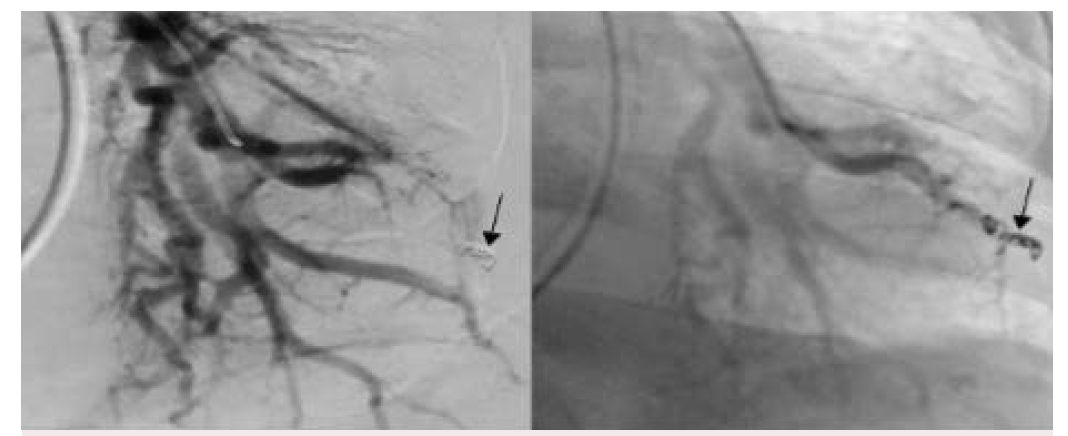

Based on CTA, the interventional radiology (IR) team was consulted, and they performed a pulmonary angiography. A large pseudoaneurysm arising from a left lower lobe segmental pulmonary artery branch was found (Figure 1), and it was successfully embolized (Figure 2).